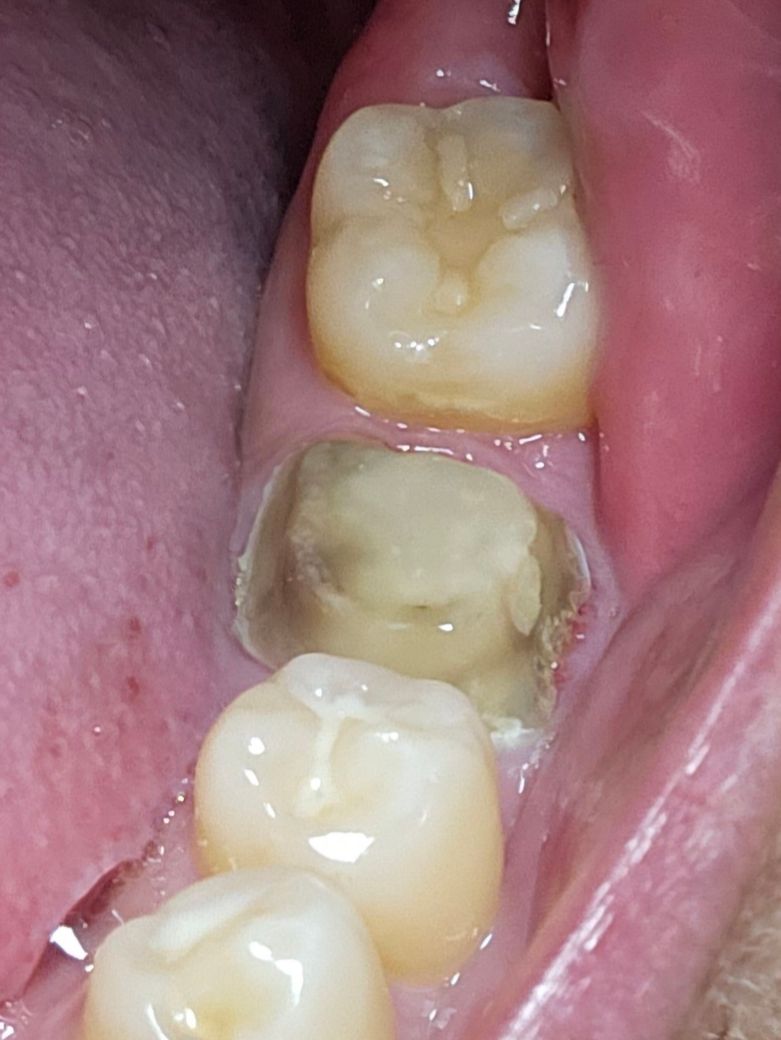

크라운이 빠졌는데 이빨이 까맣게 변해있어요

신경치료하고 크라운 씌운지 1년도 안됐는데 크라운이 밥 먹다가 빠졌어요. 크라운에서 편도결석 냄새도 나고 이빨은 사진처럼 검게 변했어요 코어 부분은 그나마 괜찮은거 같은데 원래 제 이빨이었던 부분들은 검게 변했는데 뭐가 잘못된걸까요?

사진으로만 봤을 경우에 검은색은 충치라기보다도 치아색이 착색이 된 것일 가능성이 높습니다. 검은 부분을 모두 제거하려고 하다 보면 치아가 거의 남지 않게 되어 오히려 치아가 약해질 수 있기 때문에 충치가 아닌 착색된 부위라 함을 제거하지 않는 경우도 있습니다. 자세한 확인을 위해서 직화에서 진료를 받아보는 것을 권유드립니다

추가적인 충치가 발생하였을 가능성이 있기에 이 경우 추가적인 치료후에 크라운 치료가 필요로 됩니다. 만약 충치의 정도가 깊은 경우에는 재신경 치료가 필요로 됩니다.

크라운 내부에 내부우식이 생긴 것이 의심됩니다.

어두운 부분은 좀 제거하고 코어를 다시 한 후에

크라운을 재제작하는게 좋아보입니다.